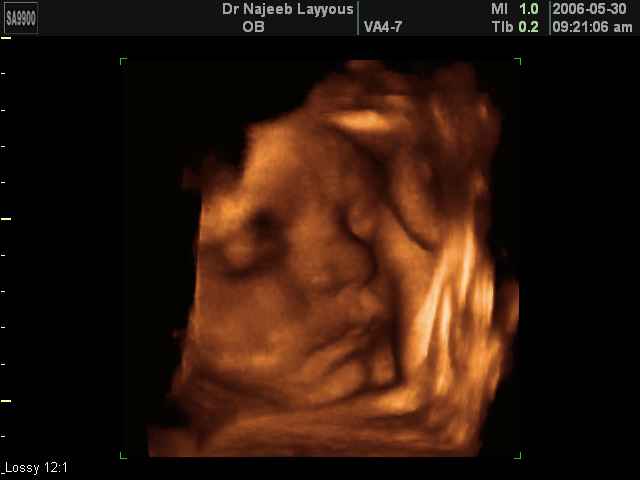

3D Fetal Face Ultrasound Scan Photos | Dr N Layyous

3D Fetal Face Ultrasound Scan Photos